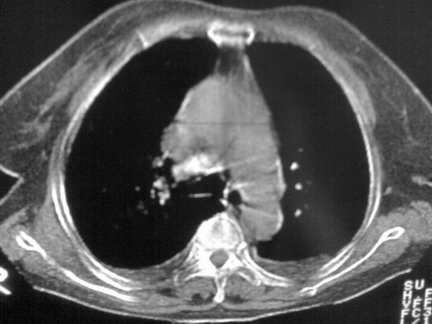

标题: CT13142:女 80 胸闷、气短、1w [打印本页]

标题: CT13142:女 80 胸闷、气短、1w

右肺炎性变,双侧甲状腺肿,胸膜肥厚。

右肺炎性变

双侧胸腔积液

缩窄性心包炎

左室为主的心脏增大。

胸膜肥厚,

气管,支气管软骨钙化。

右肺感染;双侧胸腔少量积液,心影增大,可能与心功不全有关;胸内甲状腺肿。

右肺炎性变,双侧甲状腺肿,胸膜肥厚,心影增大考虑心功能不全.

胸内甲状腺肿;右肺感染;双侧胸腔少量积液。

胸内甲状腺肿;右肺中叶感染;双侧胸腔少量积液;心影增大,考虑有心功能不全。